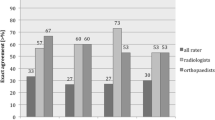

Inter-rater agreement for MRI evaluation of 32 elbows after dislocation was poor for LUCL tears, fair for RCL, moderate for AL, and fair for UCL (Table 3). Distribution of ligament tears among the two raters is described in Fig. 5. All tears were reported as complete by rater 1; 13/32 partial tears were identified by rater 2 (LUCL = 2, RCL = 2, UCL = 9).

MRI showed excellent accuracy for LUCL tears, with high sensitivity (100%), but low specificity (50%) in both raters; in the two cases of AL tears, we had found high accuracy (95.7%), sensitivity (100%), and specificity (95%).

Accuracy for RCL tears was higher for the rater 2, whereas low specificity was recorded by both raters; accuracy UCL tear resulted moderate for rater1 and low for the rater 2 (Table 4). Correlation between surgical and MRI findings of elbow ligament tears of the two raters is reported in Table 5; inter-rater agreement was good for LUCL and AL tears in both raters. Agreement for RCL tear (Fig. 3d) was poor for rater 1 and fair for rater 2; agreement for UCL tear was fair for rater 1 and poor for rater 2. Intra-operative findings of the 23 elbows included ten RHFs (type I in 6 and type IV in 4) and ten CFs (type I in 6 and type II in 4). LUCL tears were found in the four cases of type II RHFs and in 3/4 cases of CFs. Bone injuries and ligament tears were not significantly associated.

The results of this study demonstrated a good reliability of MRI scan to predict LCL injuries. Accuracy and sensitivity resulted high for LUCL and AL tears and good for RCL tears. The variable value of specificity recorded for all LCL components should be interpreted with concern due to the small size of the sample. The more controversial and less reliable issue was the MRI detection of UCL tears by both raters, although the orthopedic surgeon appeared to be more accurate compared with the musculoskeletal radiologist. Regarding the reliability of UCL findings, similar considerations apply since related to the need of a larger population and a larger sample of elbows with medial side injuries. Inter-rater agreement of MRI evaluation in the 32 elbows after dislocation was weak, with the exception of the moderate agreement found in the two elbows with AL tears.